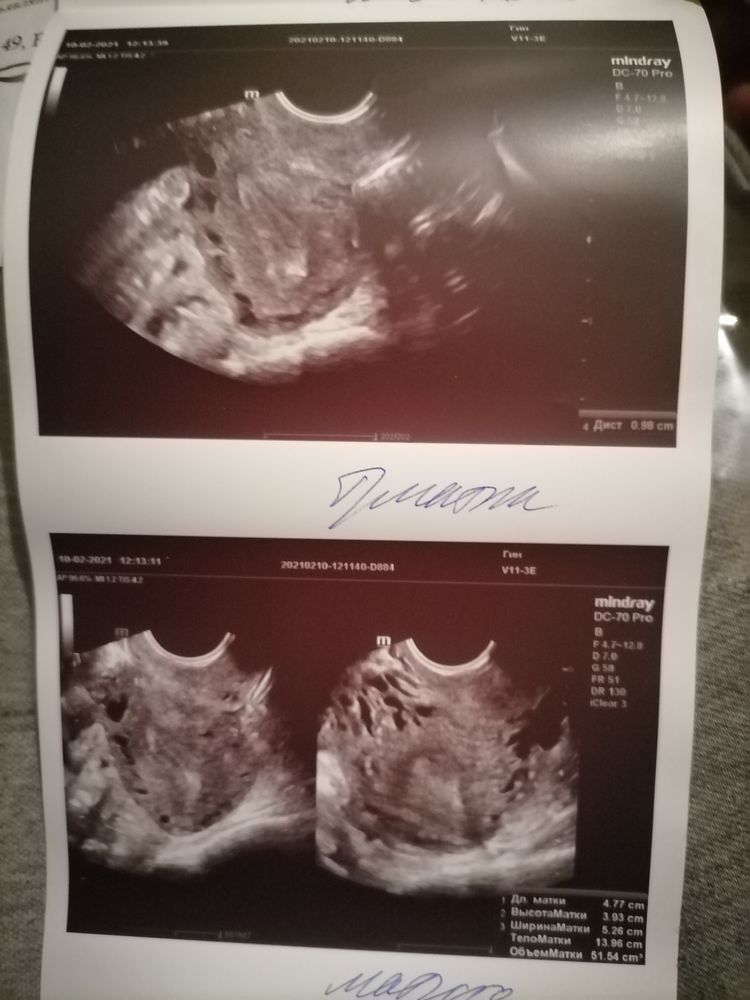

Natali, у меня варикоз малого таза есть в течении года слежу за этим, подтверждение снимки, по матке тоже разрослись

Варикоз на матке начал образовываться, но больше 6мм не растёт, но распространяется по малому тазу.